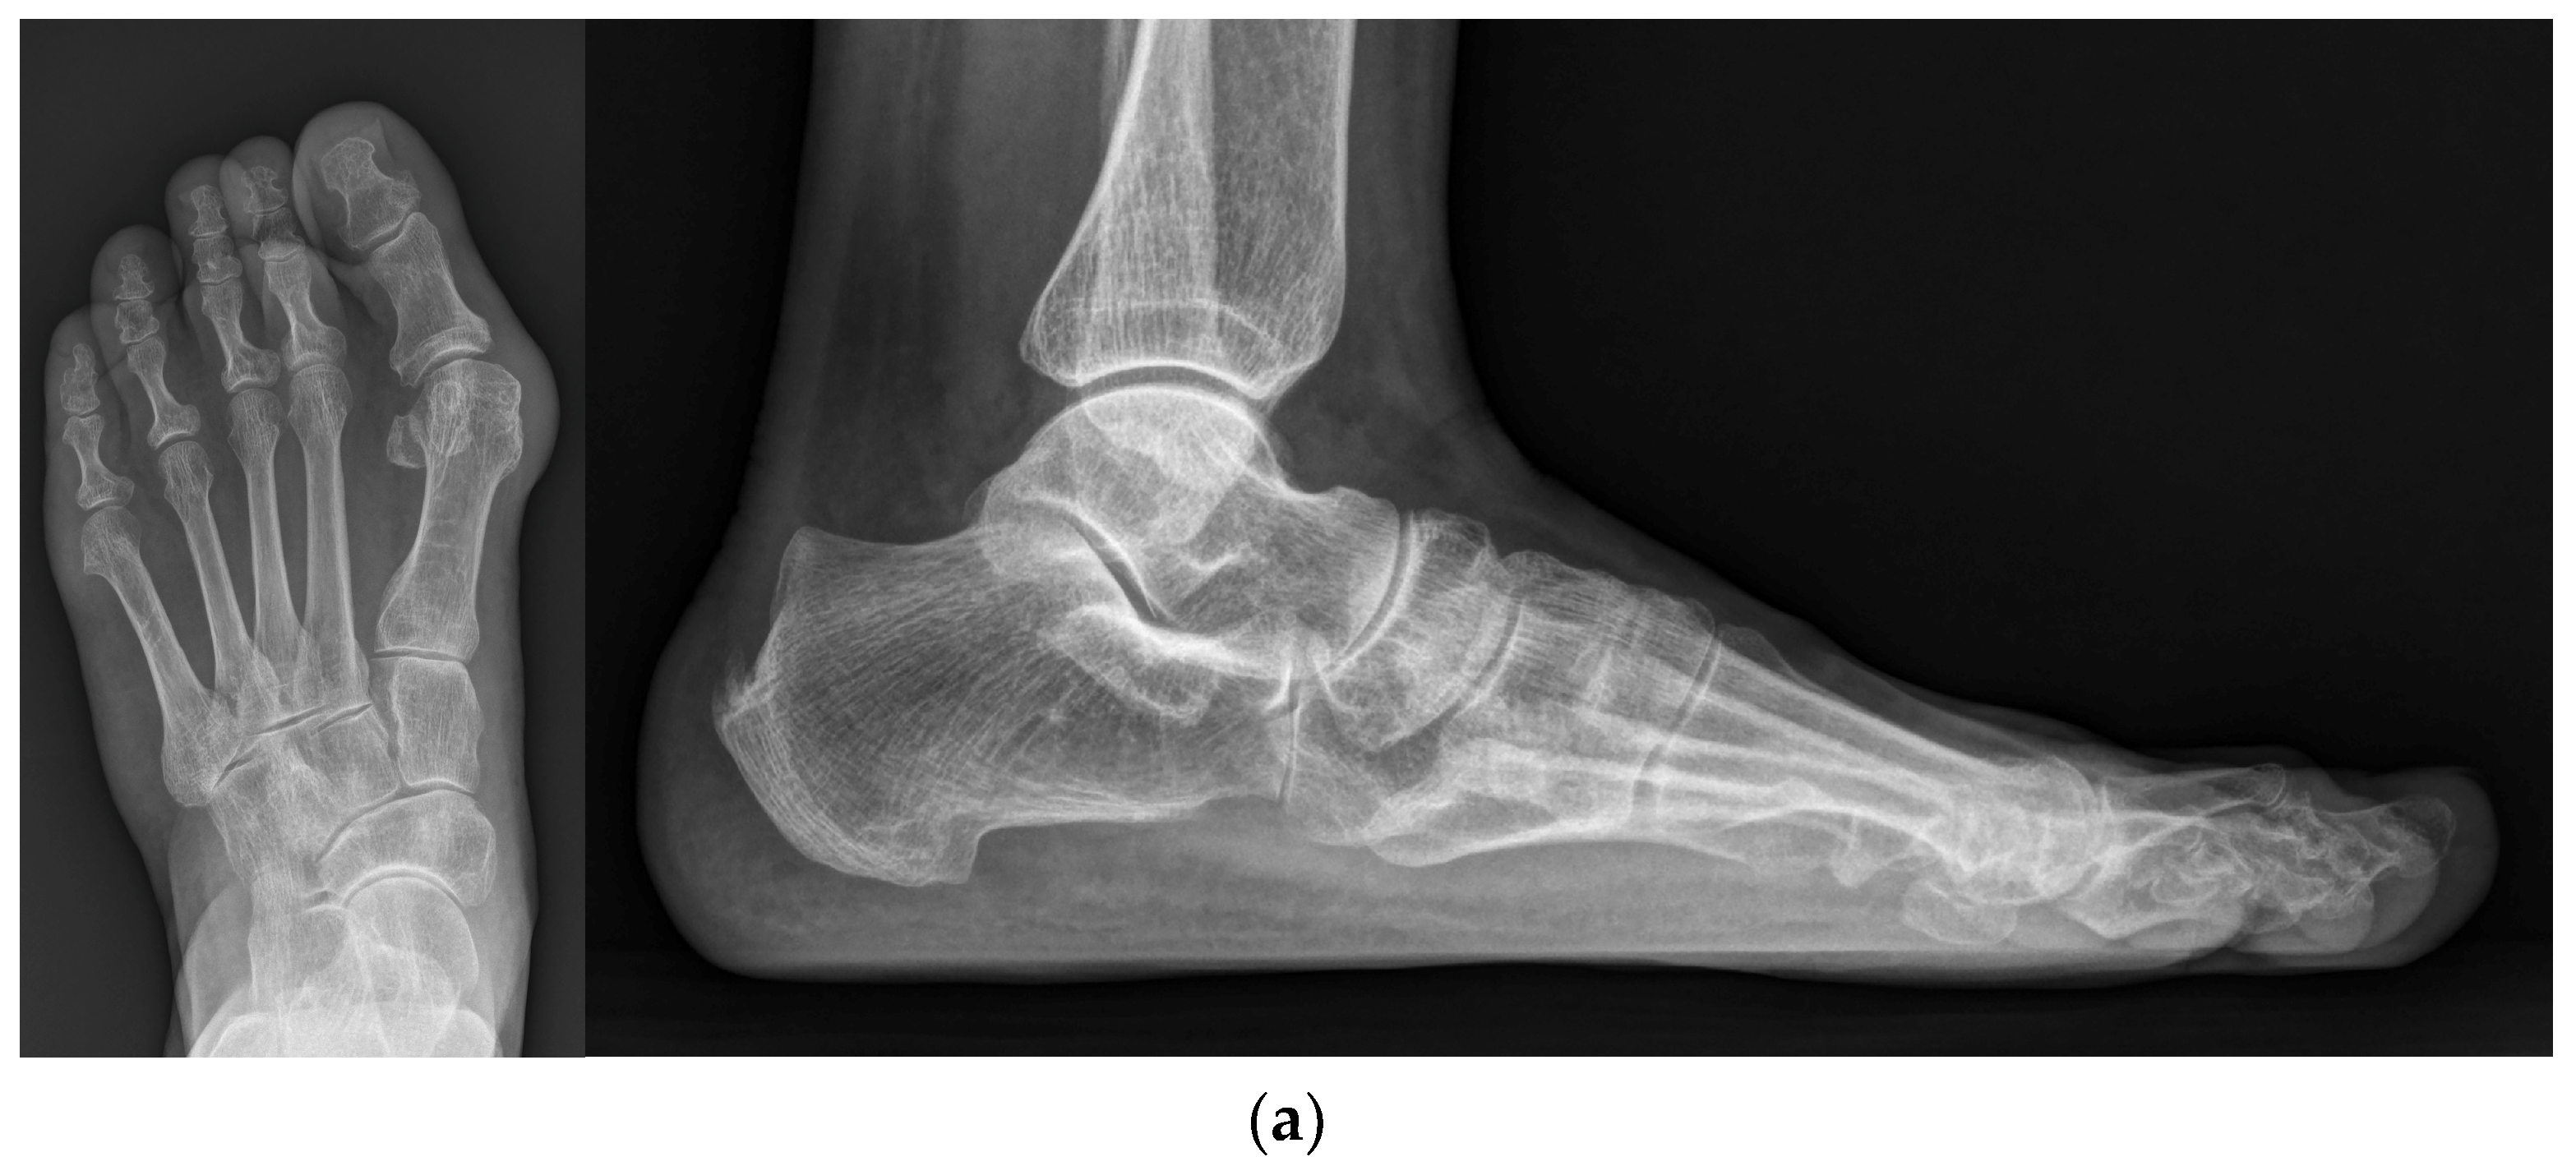

Figure 3.

(a) Preoperative standing foot anteroposterior and lateral radiographs; (b) Intraoperative foot anteroposterior and lateral fluoroscopy images; (c) Standing foot anteroposterior and lateral radiographs at 2 months post operation; (d) Standing foot anteroposterior and lateral radiographs at the final follow-up.

A bunion at the medial side of the foot was palpated, and a medial skin incision was made along the metatarsal from the distal one-third of the metatarsal bone to approximately 1 cm distal to the MTP joint. A careful dissection was performed to avoid injuring the dorsal and plantar nerves. Once the capsule of the MTP joint was visualized, a hexagonal-shaped incision (Figure 1a) was created to expose the joint and medial protrusion. In addition, a 1 cm additional linear capsular incision was made along the metatarsal longitudinal axis extending from the apex of the hexagon. The thickened capsule was excised, and the protruded bunion was resected carefully using a saw (Figure 1b). After exposing the cancellous portion of the metatarsal head area, a 90-degree osteotomy plane was drawn (Figure 1c), followed by complete osteotomy with a saw. Using a small towel clip, the proximal metatarsal fragment was pulled medially, while the capital fragment was translated laterally to the desired degree of correction, and an attempt was made to maintain the impacted position between fragments (Figure 1d). Simultaneously, a temporary 1.5 mm K-wire was inserted from the proximal to distal direction to hold both fragments (Figure 1e). Then, a 2.4 mm cortical screw was inserted from the dorsal to plantar directions to achieve firm fixation (Figure 1f). A remnant bump on the medial side was trimmed using a saw. A schematic illustration of our modified technique is shown in Figure 2. A representative preoperative standing foot radiograph of the patient is shown in Figure 3a.

Rehabilitation protocols were as follows: (1) At 2 weeks post operation, patients were advised to make an outpatient visit for the removal of the skin suture and temporary K-wires. Taping was applied to maintain the position of the hallux. Patients were allowed partial weight-bearing with the heel using crutches. (2) At 4 weeks post operation, patients were advised to remove the taping and splint. However, a postoperative shoe brace with a soft hallux valgus brace was worn for another month. (3) At 2 months post operation, the patients were instructed to sustain activities of daily living with a full weight-bearing and wear their own shoes (Figure 3c). Figure 3d shows the radiograph obtained at the final follow-up.